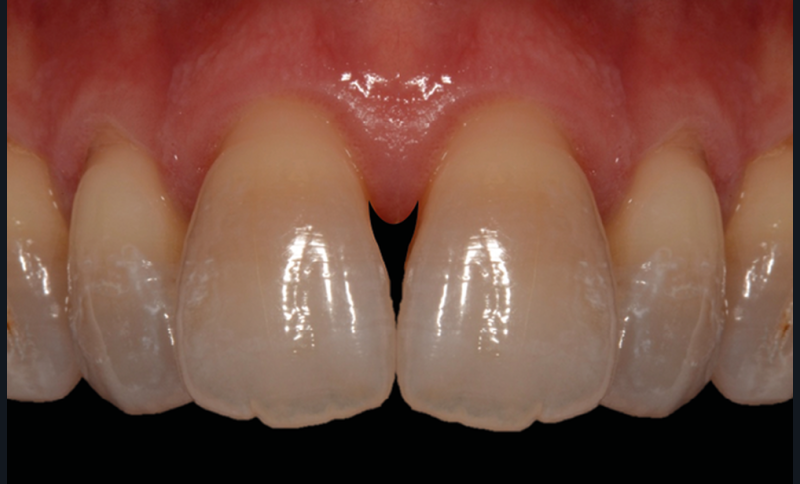

Le Pr Olivier Sorel insistera sur l’importance du respect des formes et des proportions anatomiques, pour éviter de voir apparaître, notamment chez les adultes, de très inesthétiques triangles noirs lors de la phase d’alignement (fig. 6a-b). Il présentera sa démarche diagnostique (évaluation de la forme des dents et de la dysharmonie dento-dentaire, fig. 7a-c) et l’intégration de la réduction amélaire proximale au plan de traitement, afin de s’assurer, en fin de traitement, la présence de papilles gingivales et donc d’un sourire harmonieux (fig. 8a-d).

Les Drs Marie Clément et Clara Marcoux aborderont ensuite les différents apports de la dentisterie esthétique aux traitements orthodontiques. Les problèmes de dyschromies isolées ou généralisées, congénitales ou acquises seront développés ainsi que les anomalies de proportions dentaires (dents riziformes…), le maquillage (transformation d’une canine en incisive latérale…) et le remplacement des dents antérieures. Les auteurs présenteront l’intérêt du Digital Smile Design dans le diagnostic et la communication et l’arsenal thérapeutique à notre disposition pour améliorer la satisfaction de nos patients (éclaircissement, traitement des taches de l’émail, composites stratifiés, fig. 9a-d).